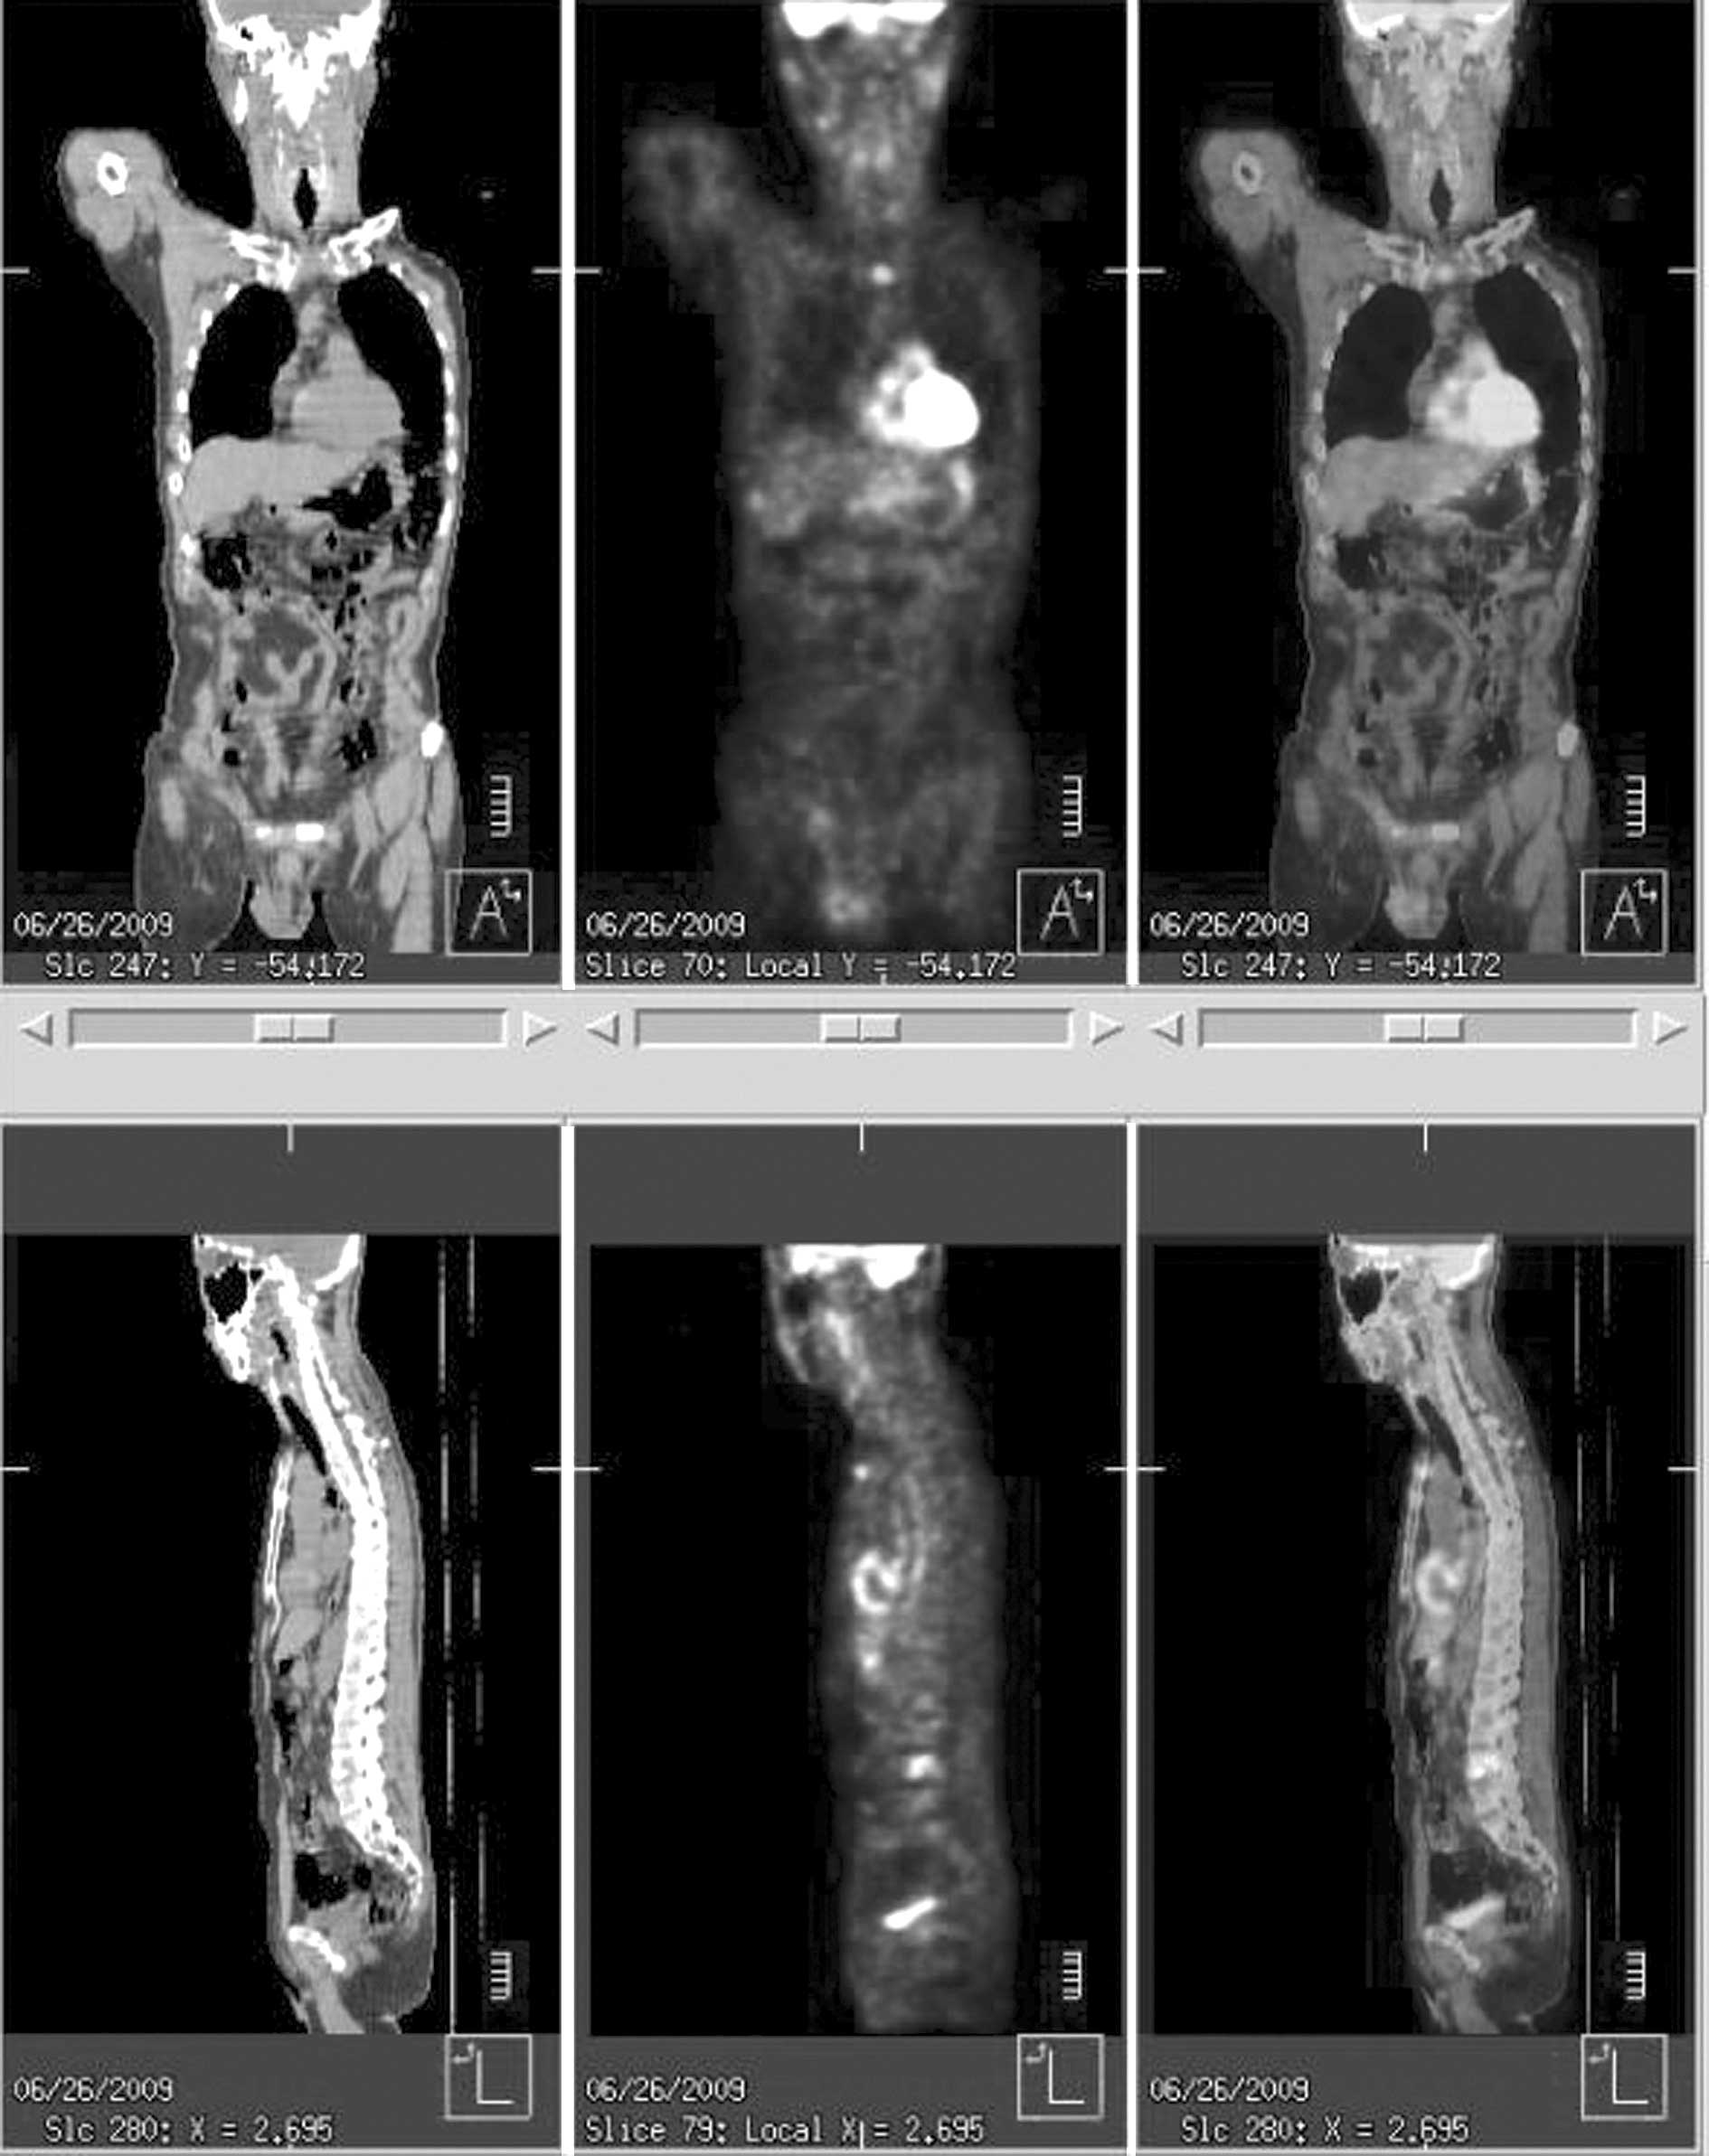

Positron emission tomography showed an increased uptake at the sternum, lumbar vertebrae, rib and retroperitoneal lymph node, with no abnormal uptake in the gastrointestinal tract (Fig. 4). The patient complained of persistent back pain, and a thoracolumbar spinal CT showed an osteolytic lesion extending into the paravertebral area at the 2nd and 4th lumbar vertebral bodies (Fig. 5). Biopsy of the oeteolytic lesion at the 4th lumbar vertebral body revealed metastatic adenocarcinoma upon pathology. A 5-FU- and cisplatin-based combination of chemotherapy and radiotherapy was administered. However, a follow-up bone scan and CT showed that the metastatic lesions had progressed, and the patient succumbed to the disease 15 months later.